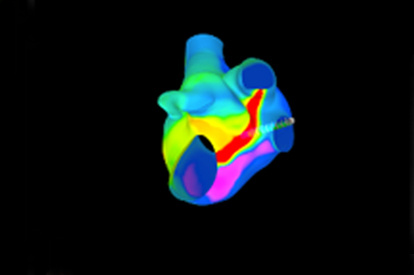

Offers true-to-life simulation of the clinical environment, including advanced imaging modalities like fluoroscopy/echocardiography, hemodynamic monitoring, medications, and interventional devices

TAVI (Transcatheter Aortic Valve Implantation) Module